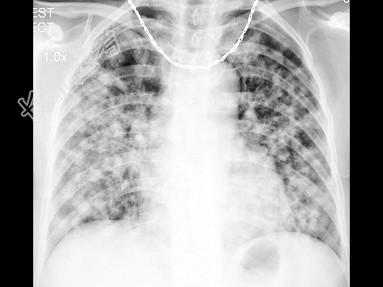

- 单项选择题女,52岁, 感胸痛2月余,无发热, X线检查如图,最可能的诊断是 ( )

A、细支气管肺泡癌

B、两肺炎症

C、亚急性血行播散型肺结核

D、肺转移瘤

E、结节病